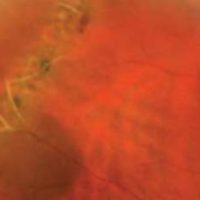

CENTRAL RETINAL VEIN OCCLUSION

Central retinal vein occlusion, also known as CRVO, is a condition in which the main vein that drains blood from the retina closes off partially or completely. This can cause blurred vision and other problems with the eye.

CAUSES

Most patients with CRVO develop it in one eye. And, although diabetes and high blood pressure are risk factors for CRVO, its specific cause is still unknown. What we do know is that CRVO develops from a blood clot or reduced blood flow in the central retinal vein that drains the retina. And we have learned that a large number of conditions may increase the risk of blood clots. Some eye doctors advise testing for them. However, it is not certain how these health conditions are related to CRVO—and some of them, if diagnosed, have no agreed-to or necessary recommended treatment.

SYMPTOMS

• Many patients with CRVO have symptoms such as blurry or distorted vision due to swelling of the center part of the retina, known as the macula.

• Some patients have mild symptoms that wax and wane, called transient visual obscurations.

• Patients with severe CRVO and secondary complications such as glaucoma (a disease characterized by increased pressure in the eye) often have pain, redness, irritation and other problems.